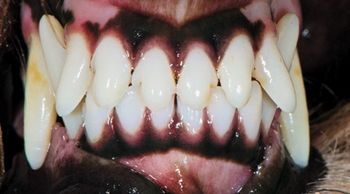

What approach would you take to fix this pups tooth and provide a solution for the long term?

Scan the photos, spot the answer and save the patient.

Extraction isn't always the best choice for veterinary patients with tooth troubles. Find out in which cases tooth repair-not removal-can restore dental health.

When is dental extraction the treatment of choice? Find out in this first installment of a multipart series on what to do to when faced with dental pathology.